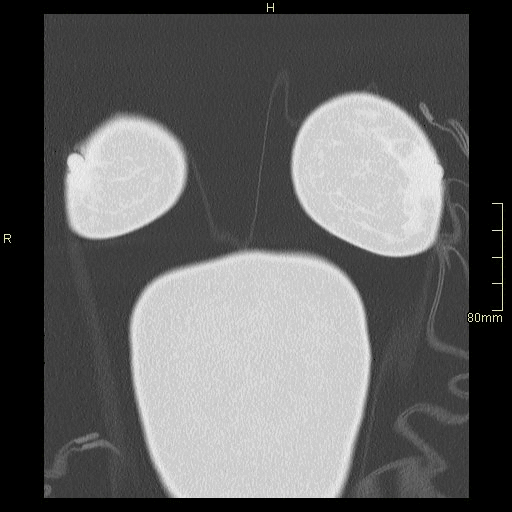

Example below is a General Chest/Abdo/Pelvis without contrast. Bony reconstructions are available depending on clinical question and differential diagnosis

Lung (Axial)